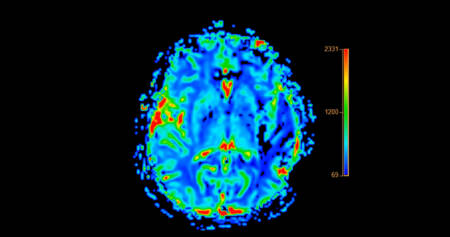

A maioria das pessoas associa o Alzheimer ao envelhecimento, mas uma pesquisa inovadora da Universidade de Columbia trouxe um dado surpreendente: sinais precoces da doença podem surgir já nos 20 e poucos anos. Os resultados, publicados na revista The Lancet Regional Health – Americas, indicam que fatores de risco normalmente analisados em idosos também impactam a função cerebral de adultos jovens.

Essa descoberta desafia a noção comum de que o Alzheimer só se manifesta tardiamente. Os pesquisadores agora defendem que o processo da doença pode estar silenciosamente ativo por décadas antes do aparecimento dos sintomas clássicos.

Os cientistas também encontraram marcadores inflamatórios e altos níveis da proteína tau total — uma das protagonistas no desenvolvimento da doença — em adultos entre 34 e 44 anos. Isso reforça que os mecanismos do Alzheimer se instalam de forma progressiva, mesmo sem sintomas evidentes.